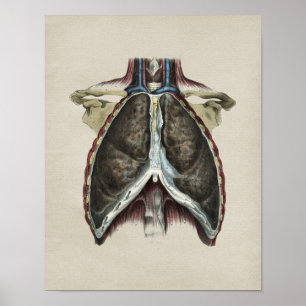

Human Internal Anatomy 1902 Print

Prijs€ 23,90

Human Heart Lungs Anatomy 1902 Print

Prijs€ 23,90

Human Heart Chest Anatomy Print

Prijs€ 23,90

Human Chest Lung Anatomy Print

Prijs€ 23,90

1850 Anatomy Print Lungs intern

Prijs€ 18,70

Poster Human Lungs Antiek Anatomie op krant

Prijs€ 49,35